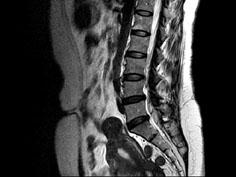

问题 女,37岁,下腹部不适,MRI检查如图所示,下列说法不正确的是 ( )

选项 A、此为子宫粘膜下肌瘤 B、此为子宫浆膜下肌瘤 C、病灶T1信号与子宫肌的信号相同 D、病灶T2信号为明显低信号 E、子宫底部局部隆起,该病灶边界清晰

答案 A